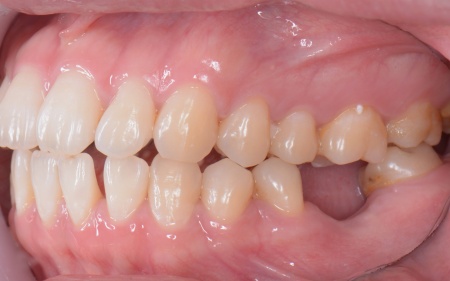

| カウンセリング | 拝見したところ、右上と左下の奥歯に強い痛みが出ていました。 レントゲンで確認した結果、どちらも歯の根が割れていることが判明しました。 歯の根が割れたまま放置すると噛むときの痛みが続くだけでなく、炎症が広がって周囲の歯や骨にまで影響を及ぼすおそれがあります。 また、上下の歯を噛み合わせた際に前歯が噛み合わず隙間ができる開咬(かいこう)と呼ばれる噛み合わせも見られました。 以上のことから、抜歯後に歯を補う治療と噛み合わせを改善するための治療が必要と診断しました。 |